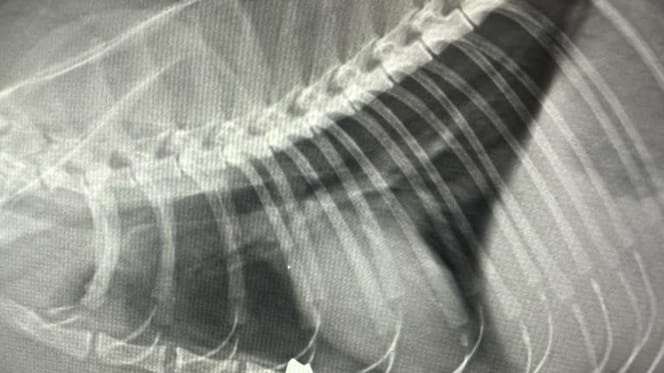

Was dann passiert, lässt selbst die erfahrene Veterinärin fassungslos zurück. Bei der äußeren Untersuchung ist nichts zu finden. Kein Blut, kein Einstich. Erst als ein Röntgenbild anfertigt wird, kommt die grausame Wahrheit ans Licht: In Mausis Brustkorb steckt ein Diabolo – ein Projektil aus einem Luftgewehr!

Das Röntgenbild zeigt, wie unfassbar viel Glück die „Glückskatze“ in diesem Unglück hatte. Das Geschoss blieb buchstäblich Millimeter vor dem Herzen stecken. Herz und Lunge wurden wie durch ein Wunder verschont. Wäre das Diabolo nur einen Winzigkeit weiter gewandert, wäre Mausi jetzt tot!